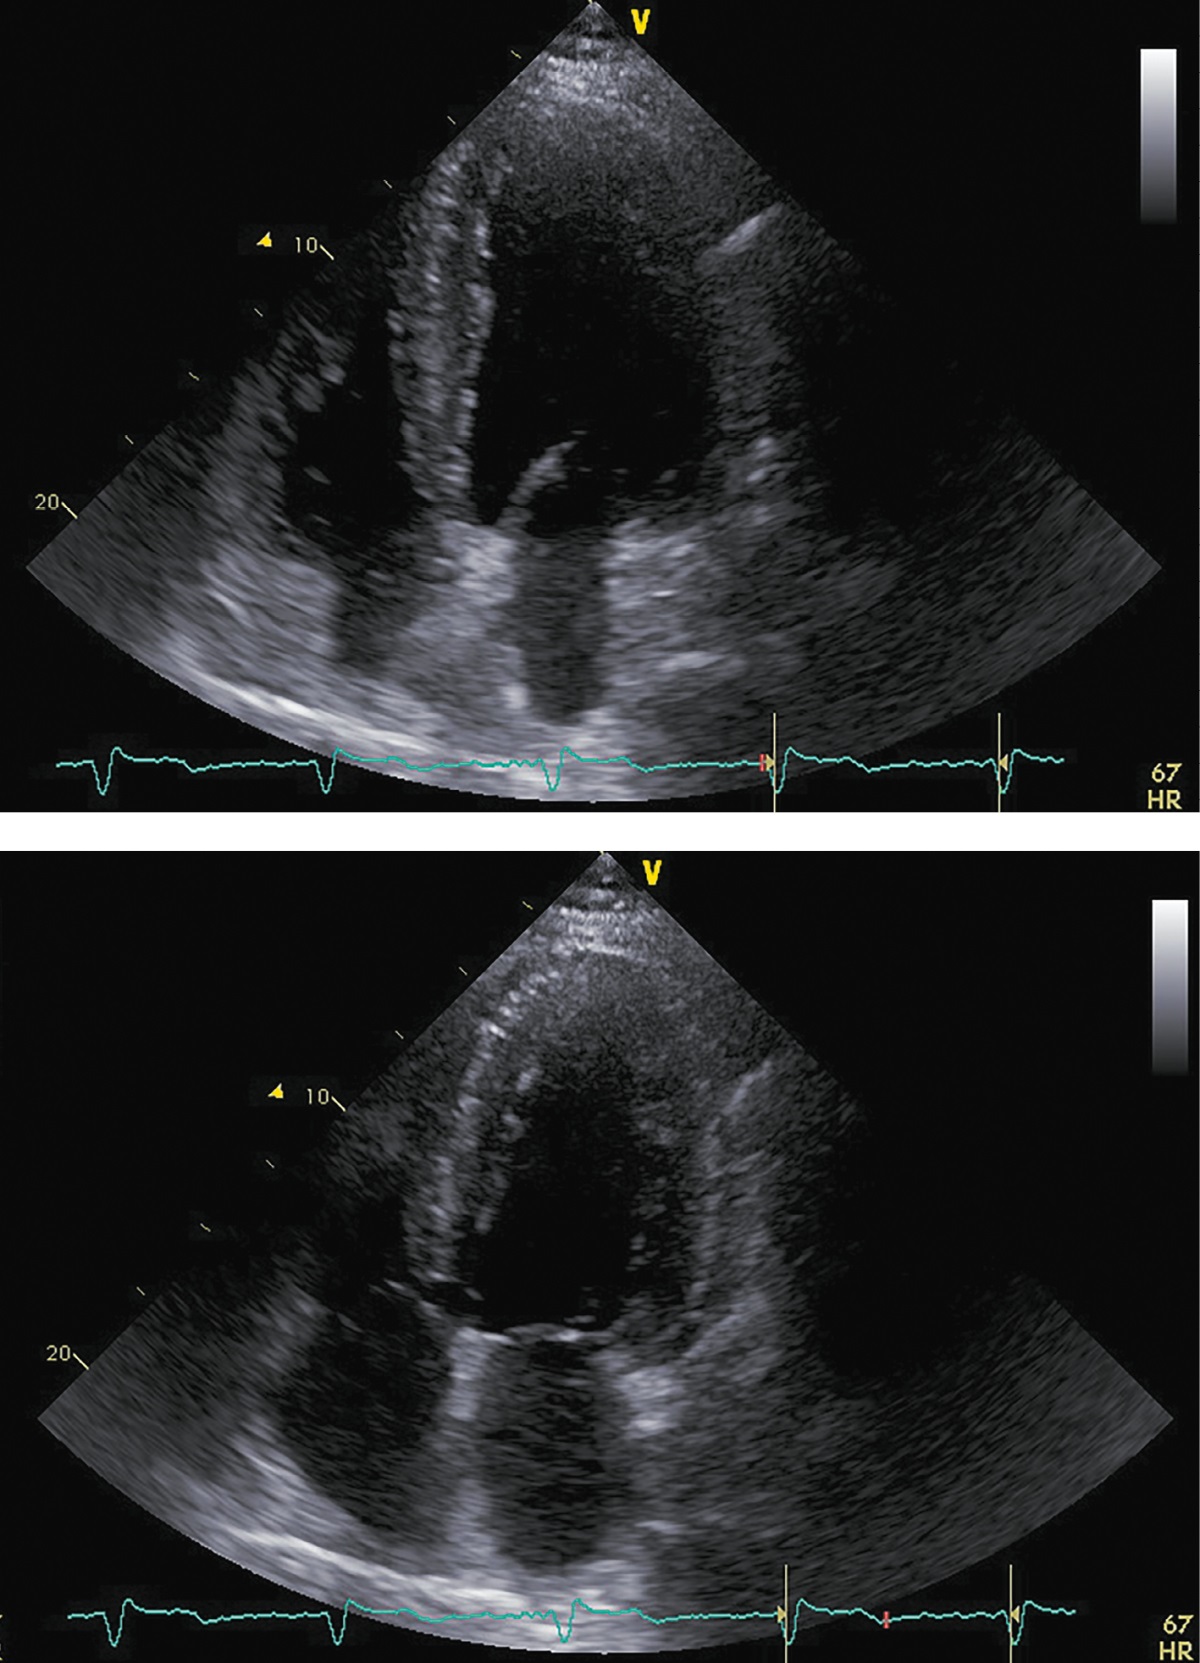

При госпитализации в октябре 2017 г. для проведения оперативного вмешательства было отмечено прогрессирование симптомов ХСН: выраженное снижение толерантности к нагрузкам с развитием одышки при минимальной физической активности, ночное ортопноэ, выраженные периферические отеки, физикальные симптомы легочного застоя (влажные хрипы в нижних отделах легких), гепатомегалия. Пациент сообщил, что получал предписанную терапию в полном объеме. На ЭХОКГ были отмечены выраженная дилатация левых камер сердца, признаки гипертрофии ЛЖ, диффузный гипокинез ЛЖ с выраженным снижением ФВ ЛЖ (19%), рестриктивная диастолическая дисфункция ЛЖ (рис. 4; табл. 2). Таким образом, несмотря на проводимую терапию, отмечено прогрессирование симптомов ХСН с дальнейшим снижением ФВ ЛЖ и развитием выраженной диастолической дисфункции. Потребовалась модификация терапии: назначение внутривенных диуретиков (фуросемид 80 мг) в течение 5 дней. После внутривенной диуретической терапии исчезли эпизоды ночного ортопноэ и физикальная симптоматика легочного застоя, существенно уменьшились периферические отеки. Постоянная пероральная терапия была модифицирована: добавлены БМКК, а также увеличены дозы пероральных диуретиков, ИАПФ, бетаАБ и кетоконазола (рис. 1). Операция была отложена на один месяц.

Рисунок 4. ЭХОКГ, 1 месяц до аденомэктомии.

Примечание: верхушечная 4-камерная позиция (сверху представлен кадр в диастолу, снизу — в систолу).

Таблица 2. ЭХОКГ-показатели, 1 месяц до аденомэктомии

|

Показатель |

Значение/индекс |

Объем левого предсердия |

135 мл/54 мл/м² |

Передне-задний размер левого желудочка |

7,20 см/2,89 см/м² |

Конечно-диастолический объем левого желудочка |

369 мл/148 мл/м² |

Конечно-систолический объем левого желудочка |

297 мл/119 мл/м² |

Локальная кинетика левого желудочка |

диффузный гипокинез |

Фракция выброса левого желудочка (усреднение по 4- и 2-камерным верхушечным позициям) |

19% |

Диастолическая функция левого желудочка |

градация III, рестриктивный тип |

Конечно-диастолическая площадь правого желудочка |

27 см²/10,8 см²/м² |

Конечно-систолическая площадь правого желудочка |

13,5 см²/5,4 см/м² |

Фракция систолического уменьшения площади |

50% |

Расчетное систолическое давление в легочной артерии |

50 мм рт.ст. |